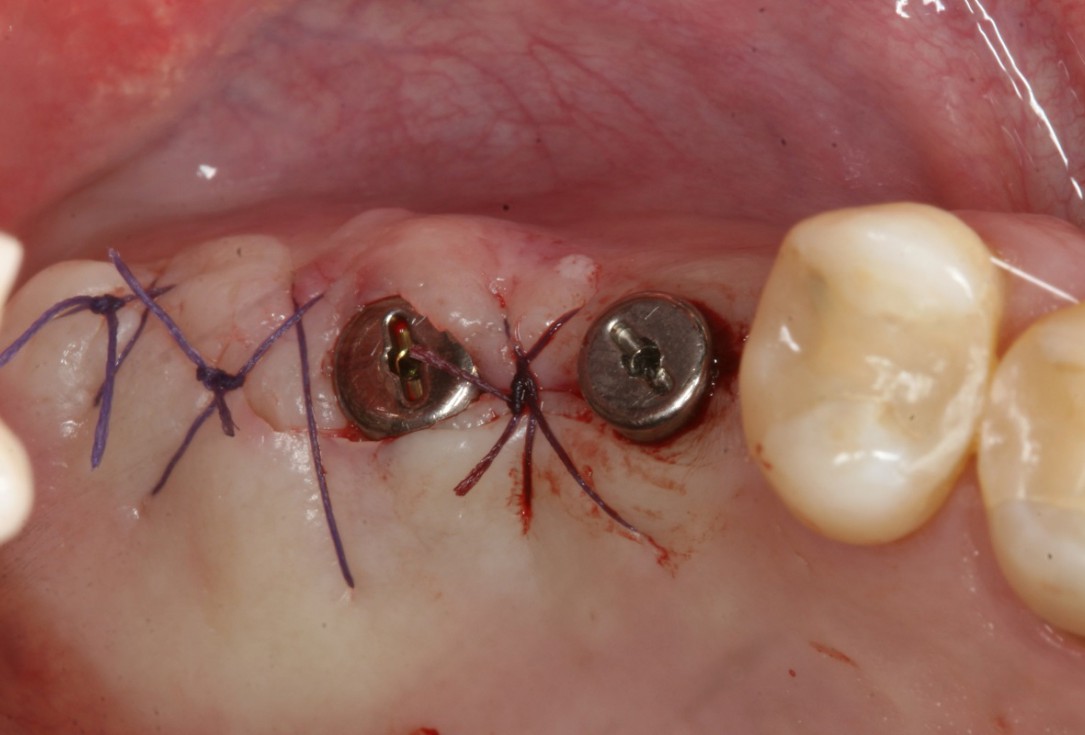

12/14 - Uncovering of implants 10 weeks post-op

Two-stage sinus lift with maxresorb® & collprotect® - Dr. S. Kistler

13/14 - Insertion of healing abutments